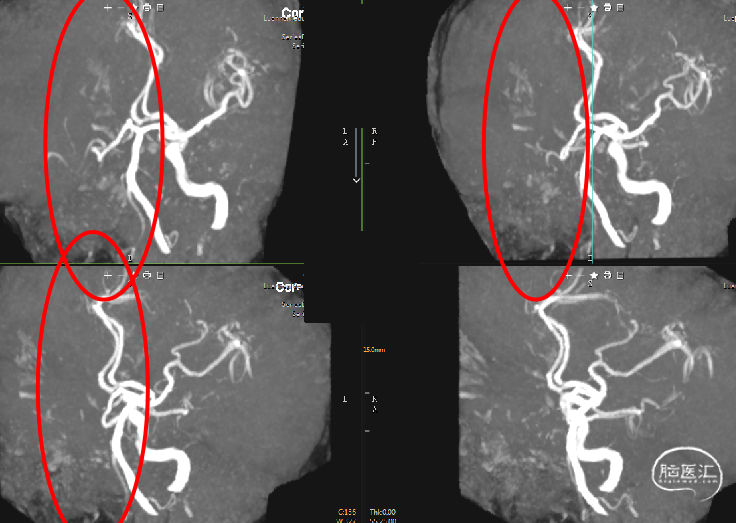

术前急诊头颅核磁共振——MRA:右侧颈内动脉缺失

急性右侧颈内动脉闭塞型脑梗死

患者头颅核磁共振提示右侧颈内动脉未见显示,考虑病变部位右侧颈内动脉,具体位置造影中分析

右侧颈内动脉闭塞,同时颈外动脉有血栓,闭塞。

右侧颈内动脉起始部呈现“火焰征”,提示假性闭塞,远端眼动脉未见代偿。

前交通开放,左侧A1供应双侧A2。

后交通动脉开放,右侧大脑中动脉可见部分显影。

提示病变为栓塞性串联病变,增加手术难度。这样我们就考虑首先争取单纯抽吸快速开通颈内动脉,然后再SWIM技术取通大脑中动脉。